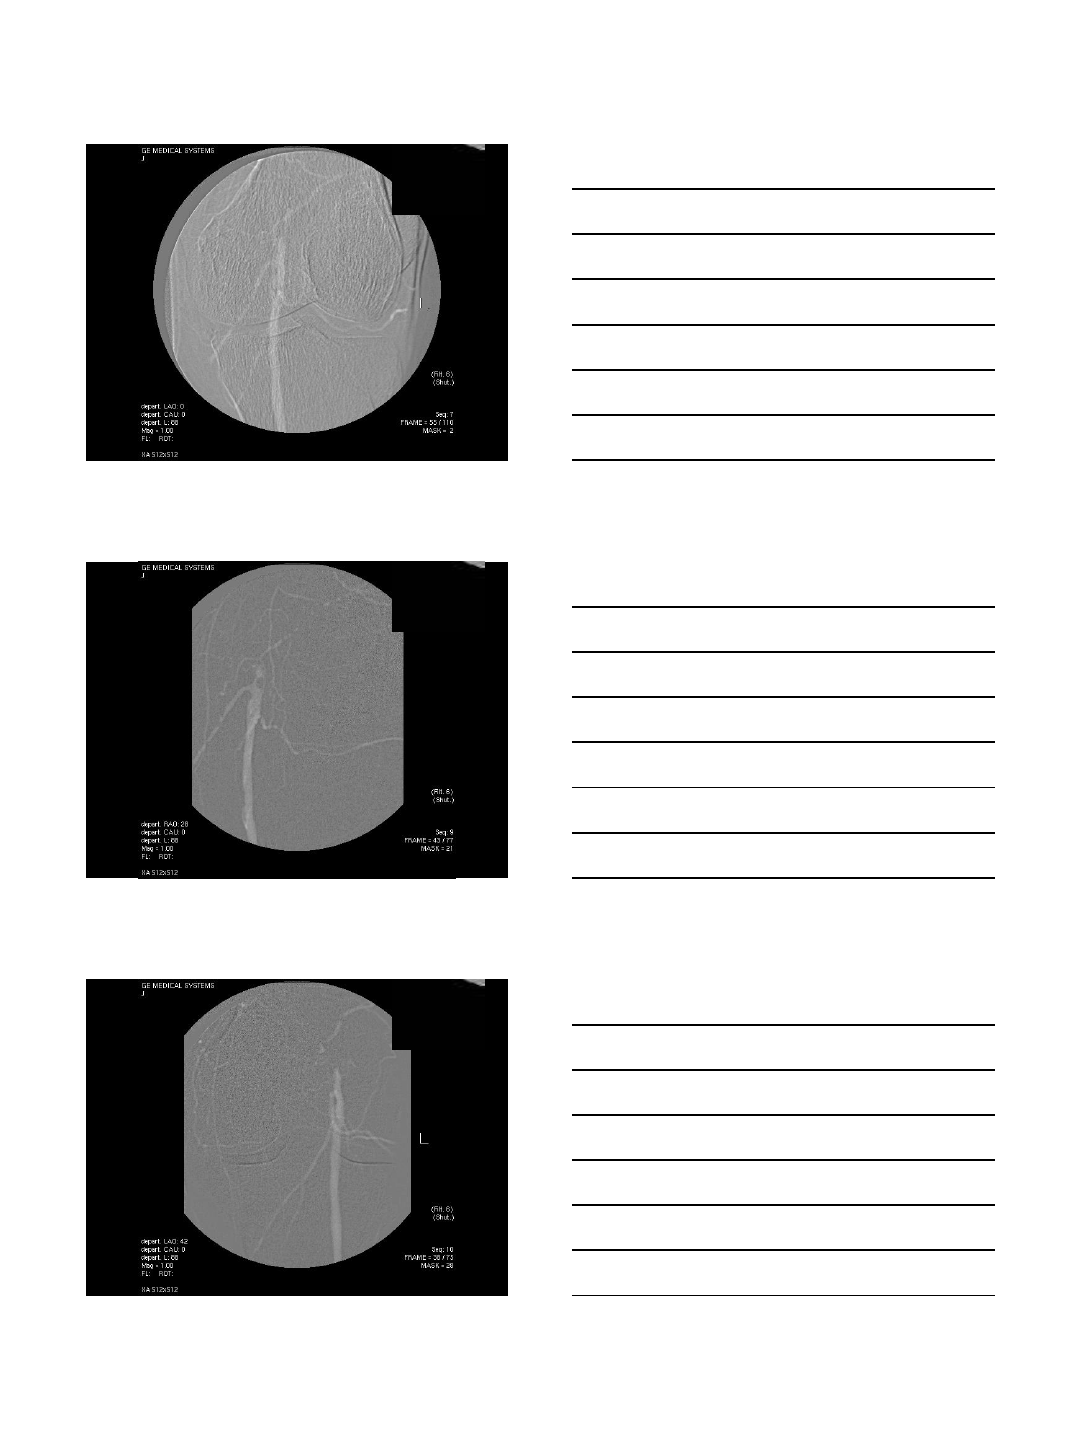

CO2 Portogram in TIPS

TIPS procedures

•AP and oblique views

•Excellent to localize the portal vein

•Wedge injection

•Wedged catheter or balloon catheter

•Gentle injection of 15-20 cc

•Careful in patients with ascites

•Intraparenchymal injection